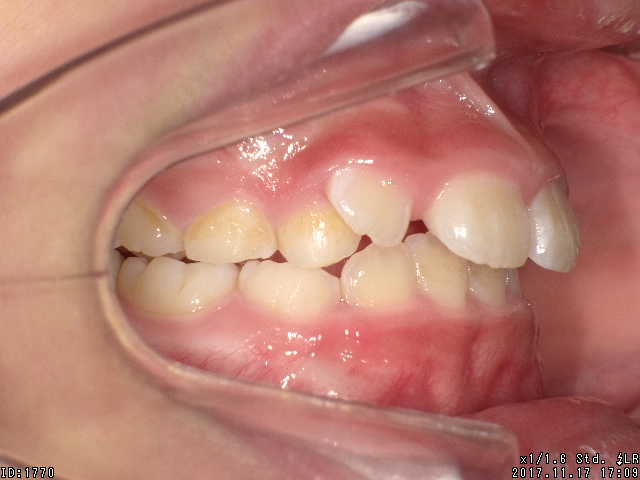

途中経過

| 症状 | 上顎前突 過蓋咬合 |

| 通院時の 年齢 |

8才1ヶ月〜15才10ヶ月 |